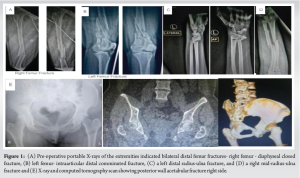

A 31-year-old female, transferred-in from another center following a high velocity trauma due to a RTA (2-wheeler vs. 4-wheeler) on June 17th, 2023, around 06:15 PM near Uran Panvel Highway. She presented with multiple fractures and internal injuries. Following the accident, patient was provided primary care at a different tertiary care center, where primary examination and first aid was performed and multiple injuries were identified. Chest X-ray and high-resolution computed tomography (CT) of thorax revealed a right haemothorax and pulmonary contusion, necessitating the insertion of an intercostal drainage (ICD) tube. Further imaging showed a Grade 3 liver injury, Grade 3 splenic injury, Grade 3 renal injury, undisplaced fracture of posterior wall of left acetabulam (Fig. 1e), and haemoperitoneum. Radiographs of extremities revealed bilateral distal femur fractures – closed diaphyseal right femur (Fig. 1a) with comminuted intra-articular left femur (Fig. 1b), left distal radius-ulna fracture (Fig. 1c), and right mid-shaft radius-ulna fracture (Fig. 1d). She also tested positive pregnancy evidenced by urine pregnancy test and a beta human chorionic gonadotropin level of 101.4.